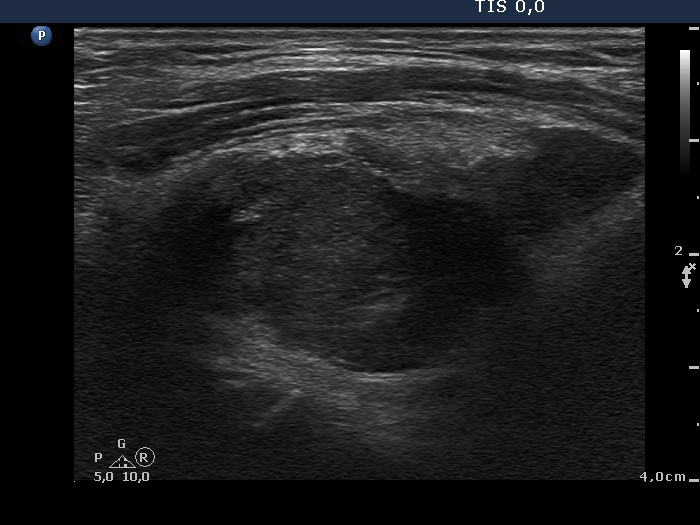

Ultrasonography. The thyroid lobes were composed of hypoechoic discrete areas. The vascularity of the thyroid was increased.

This is one of the characteristic presentations of an operated thyroid, a lobe is partly hypoechoic partly echonormal. Nevertheless, this pattern is frequently misinterpreted as nodular goiter.